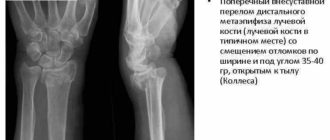

Экстензионный перелом дистального метаэпифиза лучевой кости со смещением

Лечение переломов лучевой кости Перелом «луча в типичном месте» обычно возникает при прямом падении